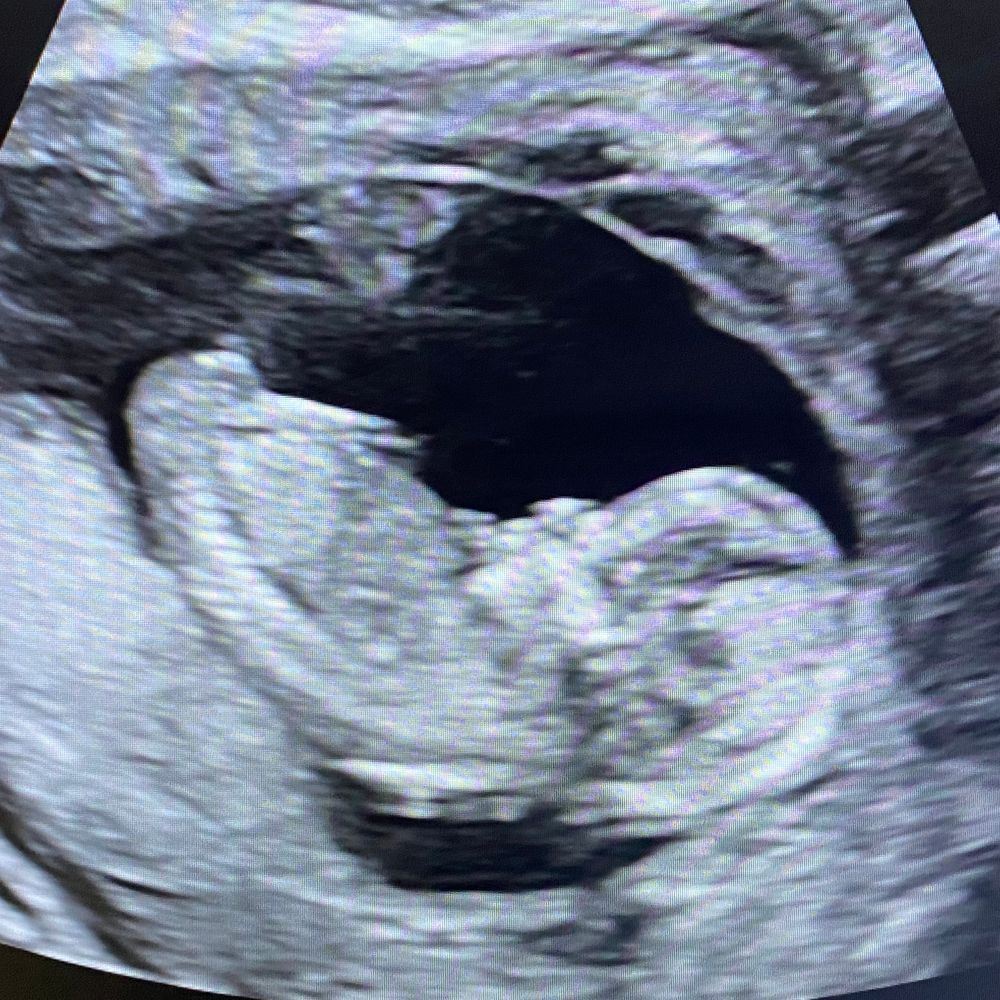

Акушерский срок 16 нед. и 2 дня

Срок беременности у меня 16-17 акушерских недель.

Сегодня была на УЗИ и узнала, что у меня будет девочка. Ходила специально так как нет сил ждать второго скрининга и любопытство взяло верх))).

Почему то мне кажется, что врач мог ошибиться, хотя и показали пипку девчачью. Сомнения есть, потому что картинка на мониторе была не такая отчетливая как в моей ЖК.